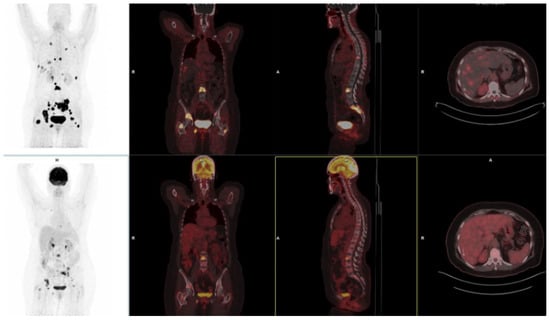

10. FAPI-Based Theranostic Approaches

11. Challenges and Limitations in FAPI Therapeutic Approaches

12. The Potential Role of FAPI PET-Based Theranostic Approaches